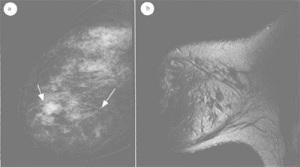

病人無意中發現乳內有一腫塊。腫瘤生長較緩慢。位於左乳內上象限及左乳內下象限者多見,也可位於乳房皮下。瘤體常單個,大小不一,呈圓形、扁圓形,界限清楚,移動良好。一般無觸痛。位於乳房皮下者,質軟,很似乳房脂肪瘤。位於腺體內者質較堅實,似乳腺增生症或乳腺纖維腺瘤,術前不易區別。該病的診斷要點為:多發生於40歲以上女性,腫瘤呈圓形、橢圓形,有包膜,質較軟不均勻,生長緩慢,有時可停止生長。X線顯示在低密度基礎上出現密度不均勻的特點。腫塊細針吸取細胞學檢查有時可抽出乳汁。

腫塊細針吸取細胞學檢查有時可抽出乳汁。鉬靶X線片可見腫物處乳腺組織密度增高,瘤體的結構和形態清晰,呈圓形或橢圓形,邊緣光滑,界限清楚。腫物密度不均,外有緊密的包裹,乳腺組織失去指向乳頭的三角形結構,瘤體將正常的乳腺組織推向一邊。X線片呈現密度不均的低密度區是本病的特點。